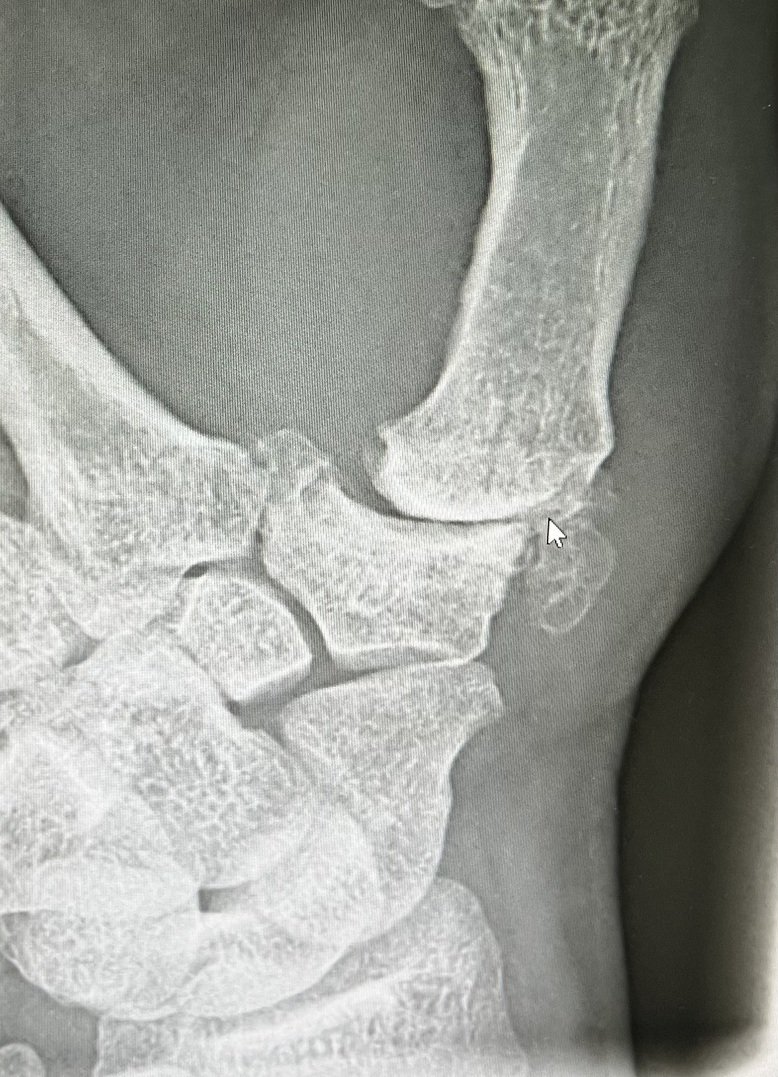

Sattelgelenkprothese Typ Touch

In unserer Praxisklinik wir bei einer Arthrose im Sattelgelenk als ein sehr erfolgreiches Verfahren eine Prothese in das Daumensattelgelen eingebaut. Wir verwenden ein sehr gutes Impantat von der Firma Medartis und zwar die Touch Prothese.